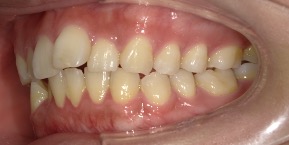

26歳女性のビフォーアフター

| 診断 | 空隙,叢生 |

| 治療方針 | 治療方針:前歯の咬合関係改善と空隙閉鎖を主な目的にて主にIPR(歯と歯の間をわずかに削合してスペースを獲得する方法)を組み込んだ動的矯正治療を行い、空隙、前歯咬合を改善後、保定を行う。臼歯部の咬合関係はプランの都合上維持することとした |

| 治療費 ※ | 69万8千円(診断、型取り、矯正中のメンテナンス、保定装置を含む料金) |

| 治療期間 | 1年8か月 |

| リスク | 1日20時間以上マウスピースを使用できない場合、歯が動かなかったり、想定しない誤差により不完全に終わる可能性がある。装着時や食事時に痛みを伴う。歯肉退縮や虫歯になるおそれがある。また、指導通りに装着できていない場合や適切なブラッシングが出来ていないとそのリスクが高くなる。歯根が短くなることがある。ごくまれに歯の神経が損傷してしまうことがある。過去にぶつけたり深い虫歯治療をしたことがあるとそのリスクはやや高くなる。矯正後には保定装置が必要。適切な使用ができない場合、後戻りの原因となる。将来的に歯並びが動いて再矯正が必要な場合がある。舌癖(舌で歯を押し出す癖)親知らずが正常に生えていない場合、その可能性がやや高くなる。 |